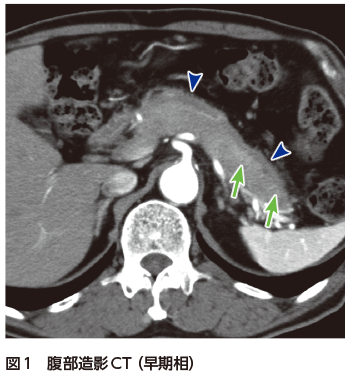

【12月スーパーSALE 15%OFF】 解答・解説】膵頭部腫瘍を指摘された60歳代男性|実践!画像診断 健康・医学の詳細情報

解答・解説】膵頭部腫瘍を指摘された60歳代男性|実践!画像診断。Amazon.co.jp: 見て診て学ぶ膵腫瘍の画像診断 : 大友 邦, 木村。症例1:診断と解説。質の高い『膵臓がん検診 (ドック)』のすすめ -うまい秘訣は。「膵腫瘍の画像診断 : 見て診て学ぶ」木村 理定価: ¥ 12000目立つ汚れなし名前印鑑あり消させていただく予定です!#木村理 #木村_理 #本 #自然/医療・薬学・健康